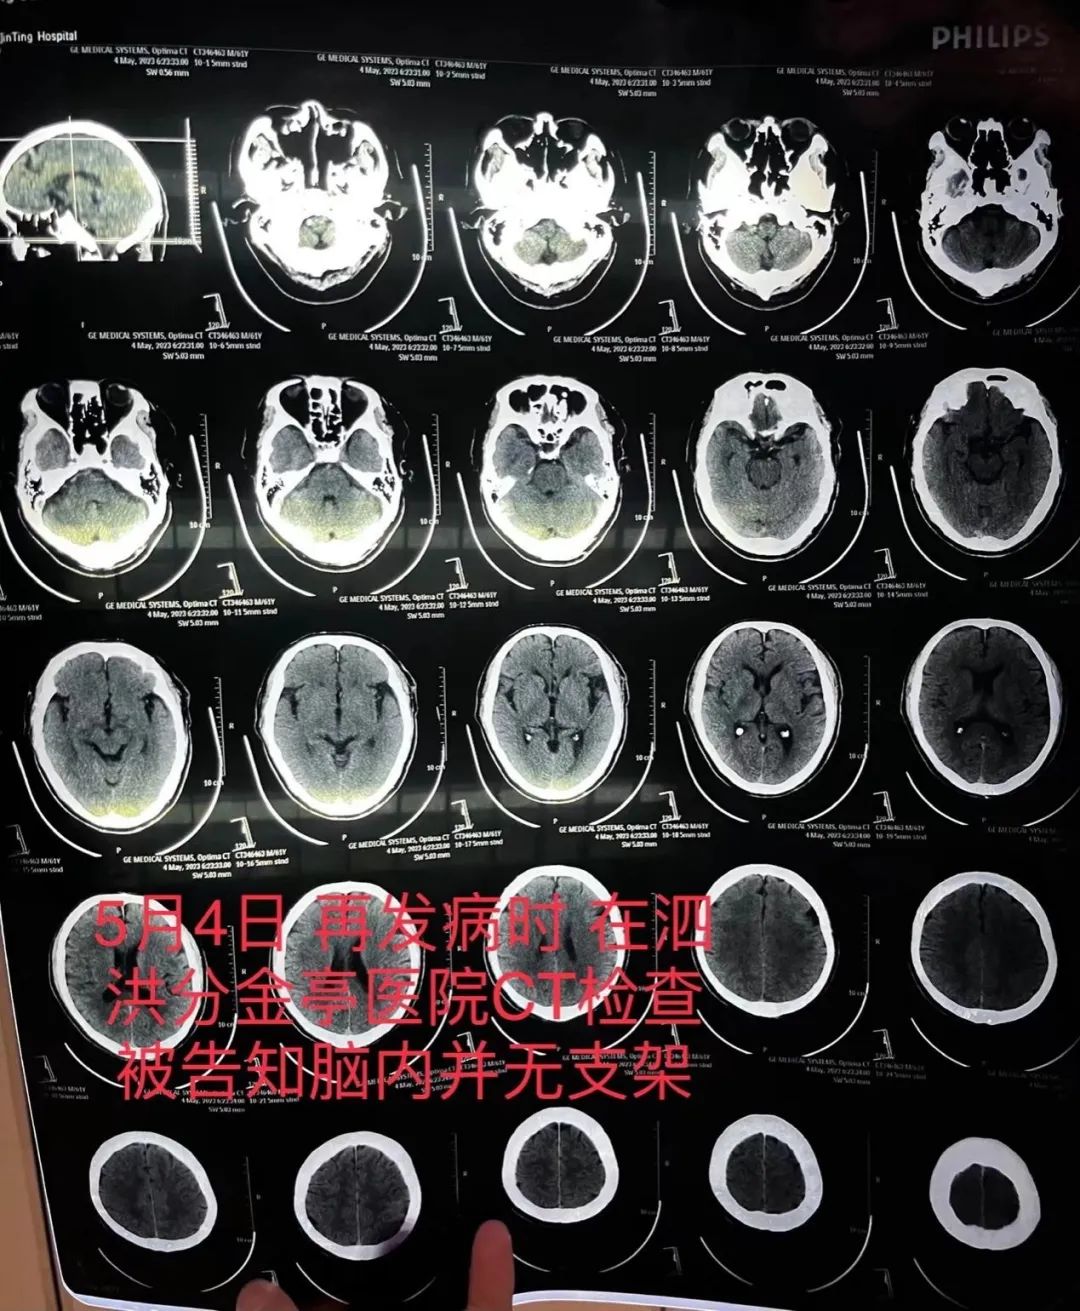

5月4日,朱老汉突发严重脑梗。他先被救护车送至江苏省宿迁市泗洪县分金亭医院抢救。令家属没想到的是,当时的CT检查发现,其颅内段部分动脉已严重堵闭,同时未发现此前植有支架。“我们当时不相信这个检查结果,认为这是小医院,可能检查不出来,所以我们决定转送到之前的医院。”朱先生说,朱老汉又被转入宿迁第一人民医院,曾作为主刀医生的齐某此时才承认,之前未能在患者颅内血管成功植入支架。

C

T检查报告显示颅内并无支架